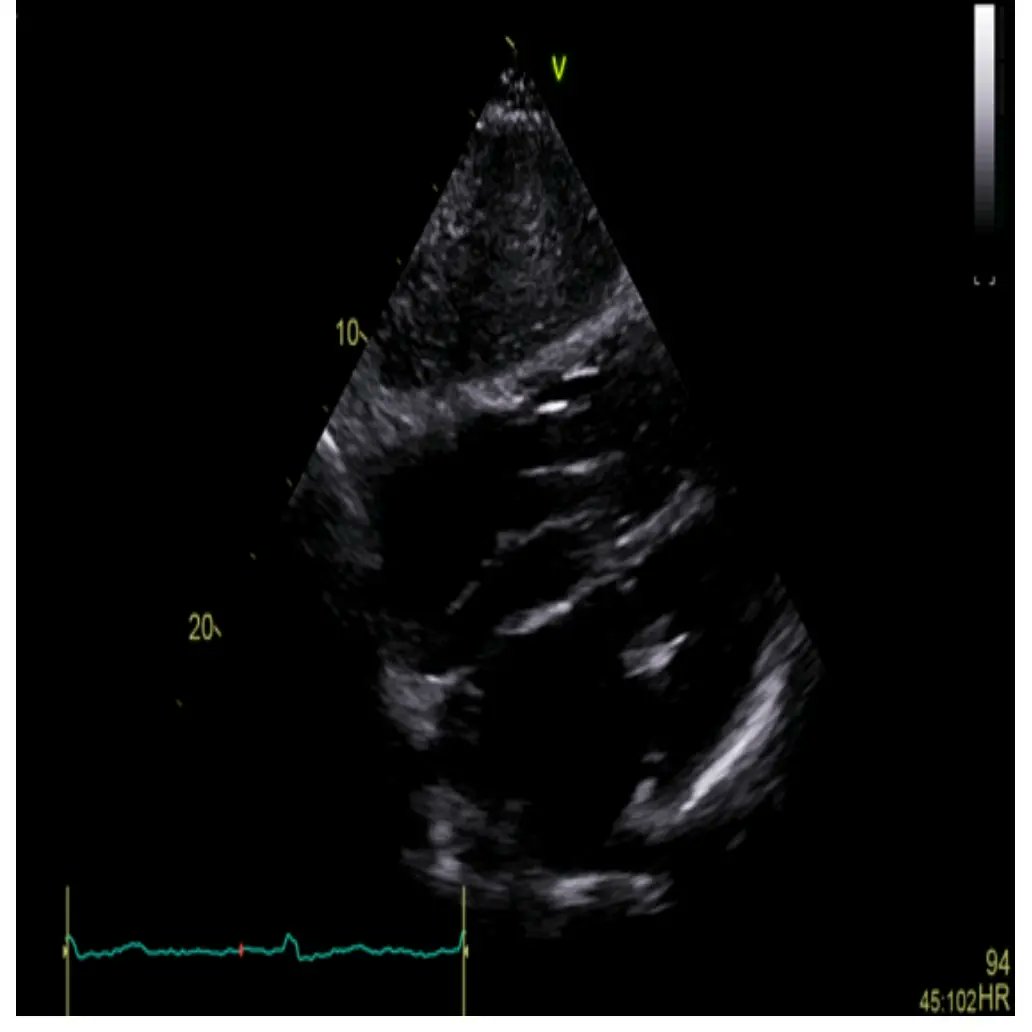

🫀 RISCONTRO OCCASIONALE DI TROMBO IN AURICOLA ATRIALE DESTRA IN UN GIOVANE PAZIENTE CON SCOMPENSO CARDIACO CONGESTIZIO E IN RITMO SINUSALE🫀